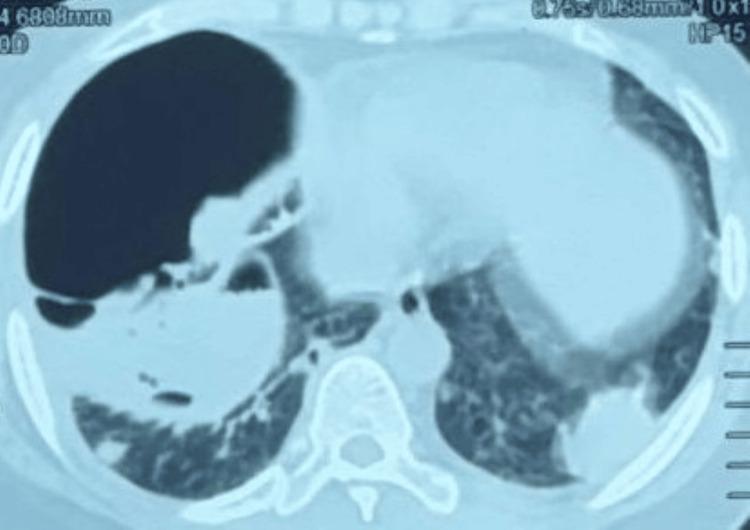

类风湿关节炎所致复发性继发性自发性气胸:1例罕见病例报告

继发性自发性气胸通常由肺结核或肺气肿引起。其他病因包括间质性肺疾病、尘肺病、机化性肺炎以及罕见病症,如朗格汉斯细胞组织细胞增多症和淋巴管平滑肌瘤病。类风湿性关节炎是复发性继发性自发性气胸的罕见病因,系由胸膜下坏死性结节破裂所致。已知甲氨蝶呤和来氟米特等药物会加速这些坏死性结节的形成和发展。尽管确切机制尚不清楚,但据信是由于单核细胞活性降低和类风湿因子增加,巨噬细胞作为一个病灶与类风湿因子相互作用形成结节,当该结节与胸膜腔相通时最终导致气胸。本报告介绍了一例罕见的类风湿性关节炎相关肺疾病患者因胸膜下坏死性结节破裂导致复发性自发性气胸的病例。